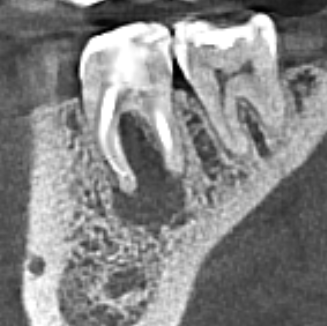

blackhead Опубликовано Понедельник в 02:54 Поделиться Опубликовано Понедельник в 02:54 Добрый день. Господа профессионалы, прошу вашей помощи по данному вопросу. Зуб не болит, рабочая 6-ка. Но все стоматологи, у кого консультировался (4 человека) говорят удалять. Один сказал, что где-то в Москве такие зубы спасают. Подскажите своё мнение, пожалуйста. Ссылка на комментарий

Doc Опубликовано Вторник в 15:23 Поделиться Опубликовано Вторник в 15:23 Если задета бифуркция (а она тут почти полностью отсутствует), то такой зуб уже не жилец. Ссылка на комментарий